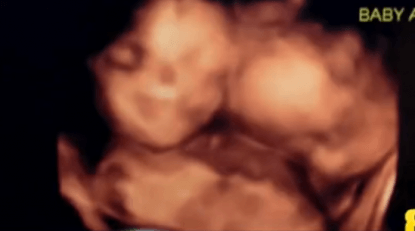

Le loro due gemelline Tatiana e Trinity sono mono mono, una condizione che si verifica 1 volta su 10 mila gravidanze.

“Sono nello stesso sacco e, una volta nate, saranno assolutamente identiche”.

Solitamente, quando si tratta di gemelli, un uovo si divide in due embrioni. Nei mono mono l’uovo si divide più tardi. I bimbi quindi hanno ciascuno il proprio cordone ombelicale, ma condividono la stessa placenta e il sacco amniotico.